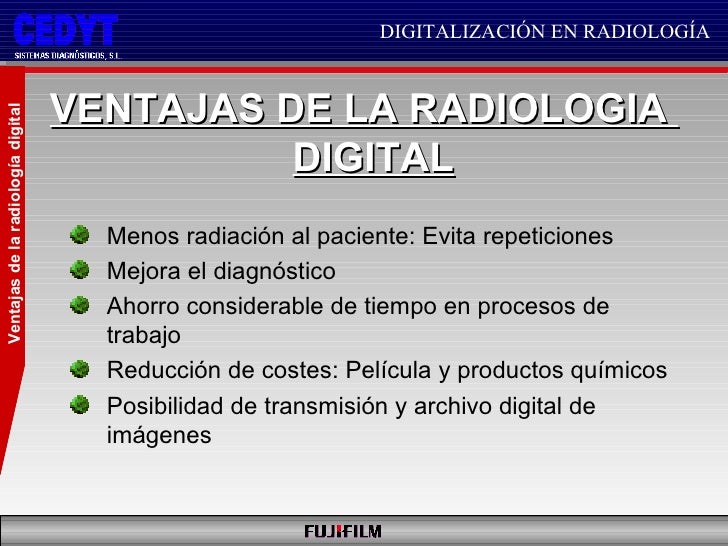

RADILOGIA DIGITAL El mayor avance tecnológico en sistemas de imágenes de uso médico de la última década.

A SUSTITUIDO AL TRADICIONAL CONJUNTO CHASIS -PELICULA CONVENCIONAL.

VENTAJAS